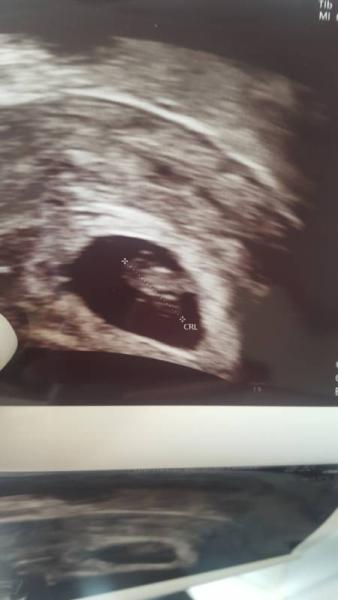

Hi Mädels, jetzt bin ich wieder zurück vom us und alles ist gut. Ich habe mein baby gesehen und das herz schlug super . Es ist jetzt 18 mm gross laut is bin ich bei 6+5 aber normal waere ich bei 7+0 aber alles gut der vorlaeufige Et ist der 23.4

Bild zu Zurück vom Us - Forum für April - Mamis

Vielen dank ich habe nur ein tipfehler drin dag ich gerade ... Das Kleine wesen ist 8.1 mm und nicht 18